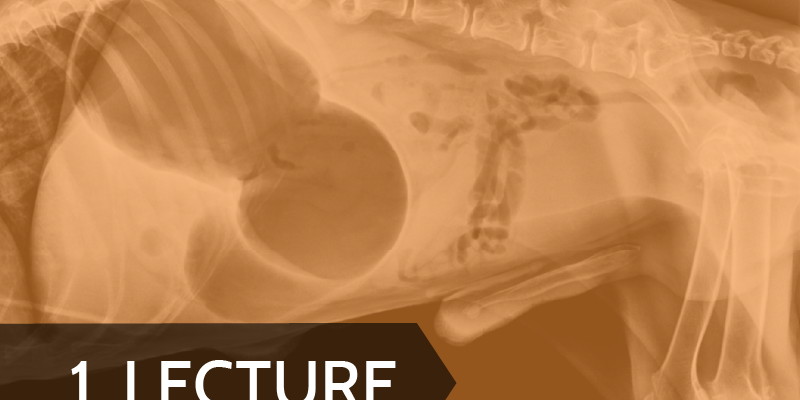

Lecture: Gastric Dilatation and Volvulus